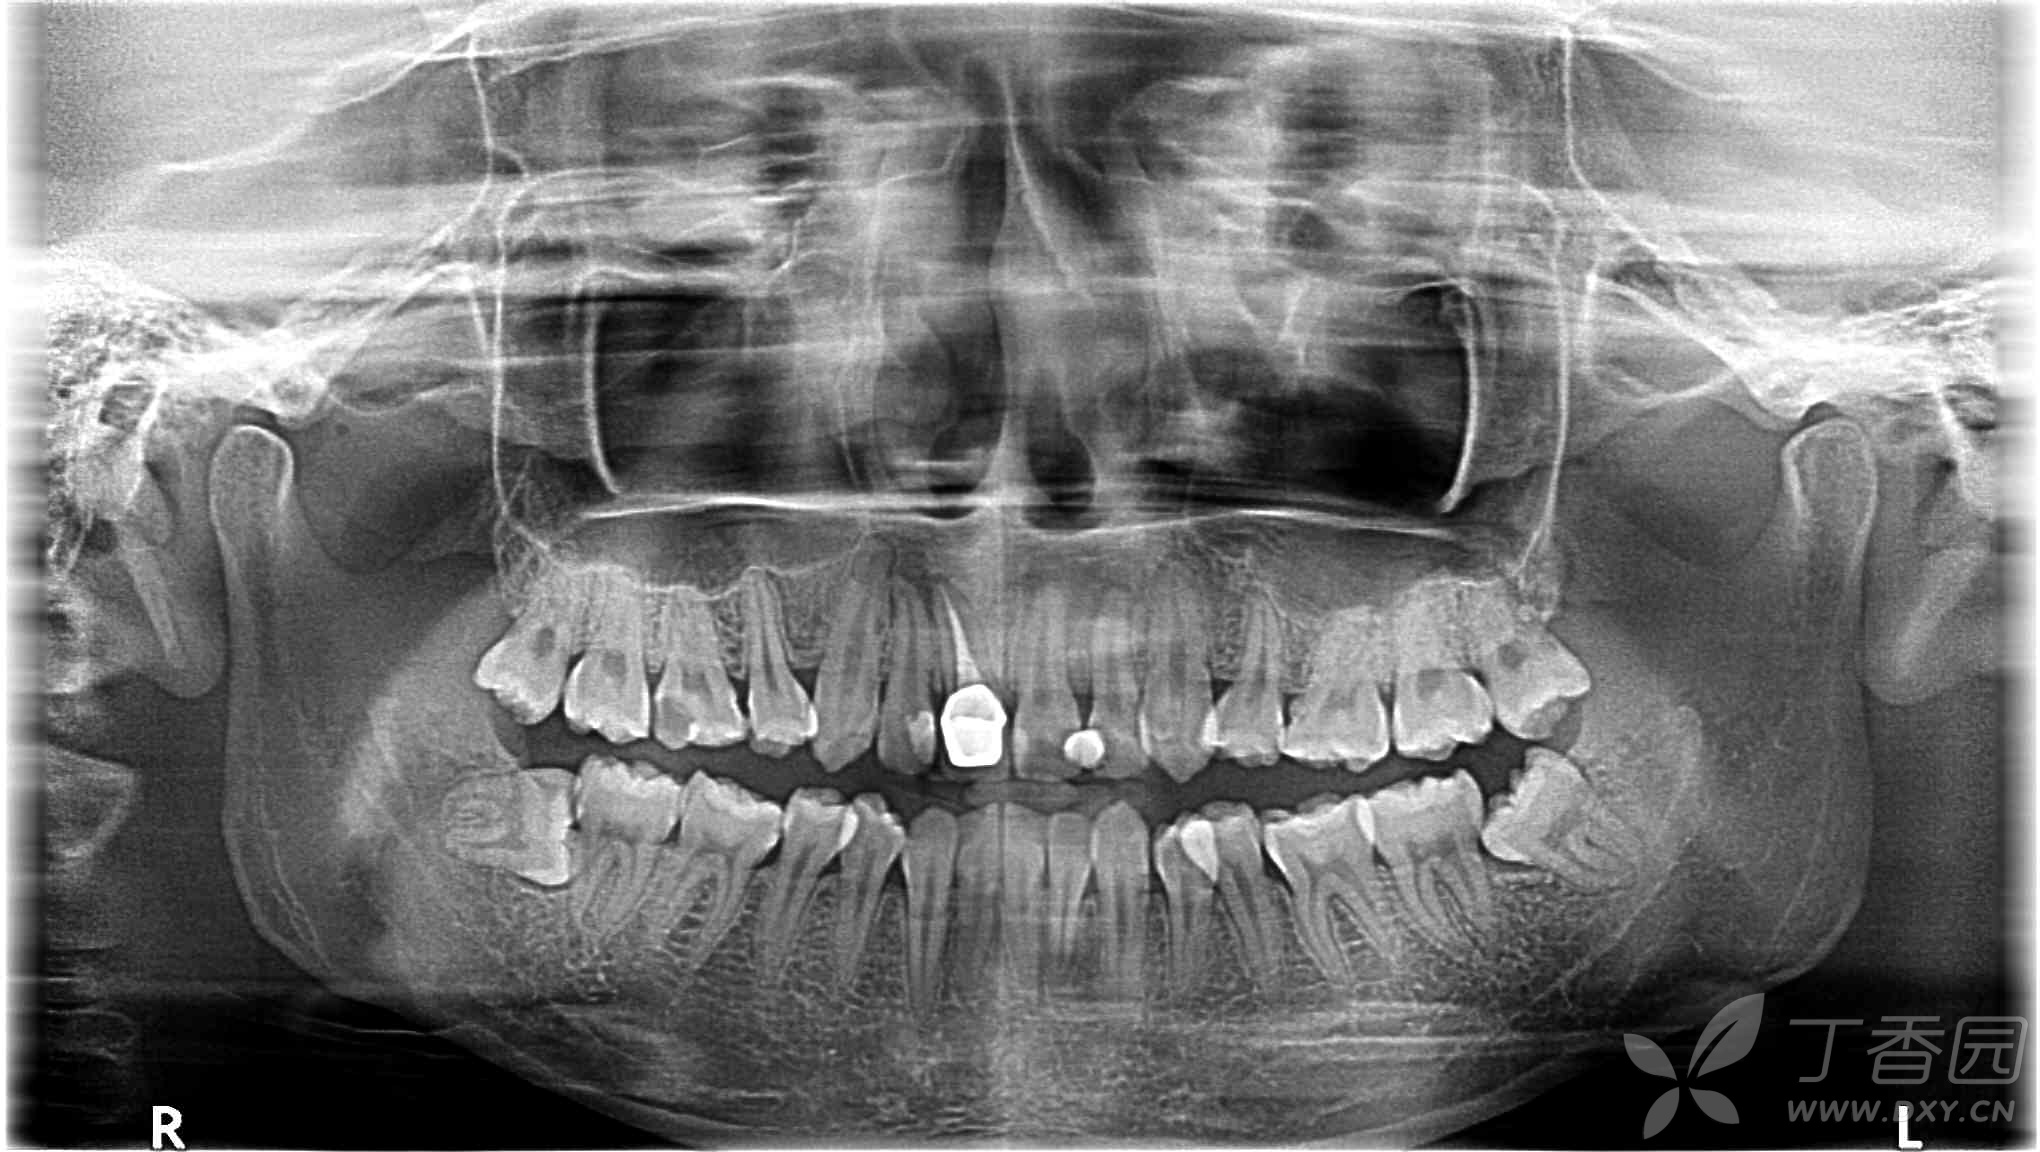

口腔全景片看分解图

口腔全景片看分解图,口腔全景片解剖结构

口腔全景片

口腔全景片解剖结构

新手看口腔全景片图解

口腔全景片解剖

口腔全景片解剖标志

口腔全景片图解

口腔全景片25个解剖点

口腔全景片怎么看图解

口腔全景片解剖图解

口腔全景片读片内容